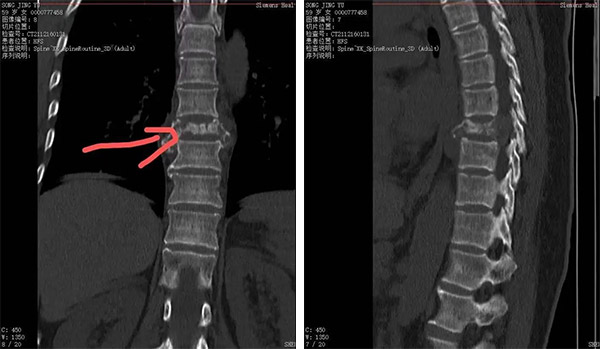

胸8椎体病理性骨折,溶骨性破坏

胸8水平脊髓受压